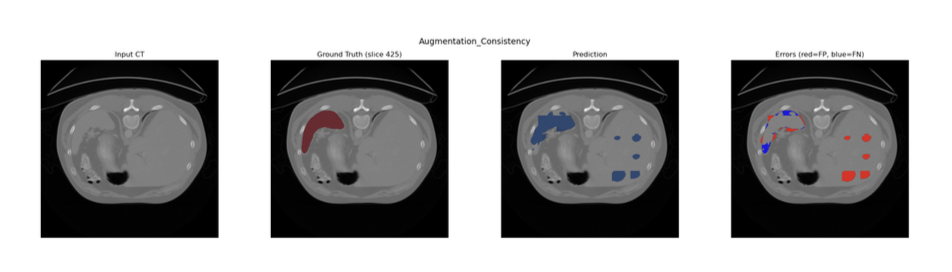

Model D and E

- Attention U-Net with Augmentation Consistency:Augmentation Consistency Technique (where volumes are variabily augmentated and passed through the same model for prediction) used to futher enhance model's performance

To leverage the abundance of unlabelled image volumes, an augmentation consistency framework was integrated. The training loop was partitioned into two streams:

1. Supervised - Labelled patches were passed through the network without additional augmentation

2. Unsupervised - Two independent augmentations were applied to the same unlabelled patch. Both augmented views were passed through the current model under gradient isolation; the MSE between the two resulting predictions was computed as the consistency loss and scaled by λ = 0.01 before backpropagation.